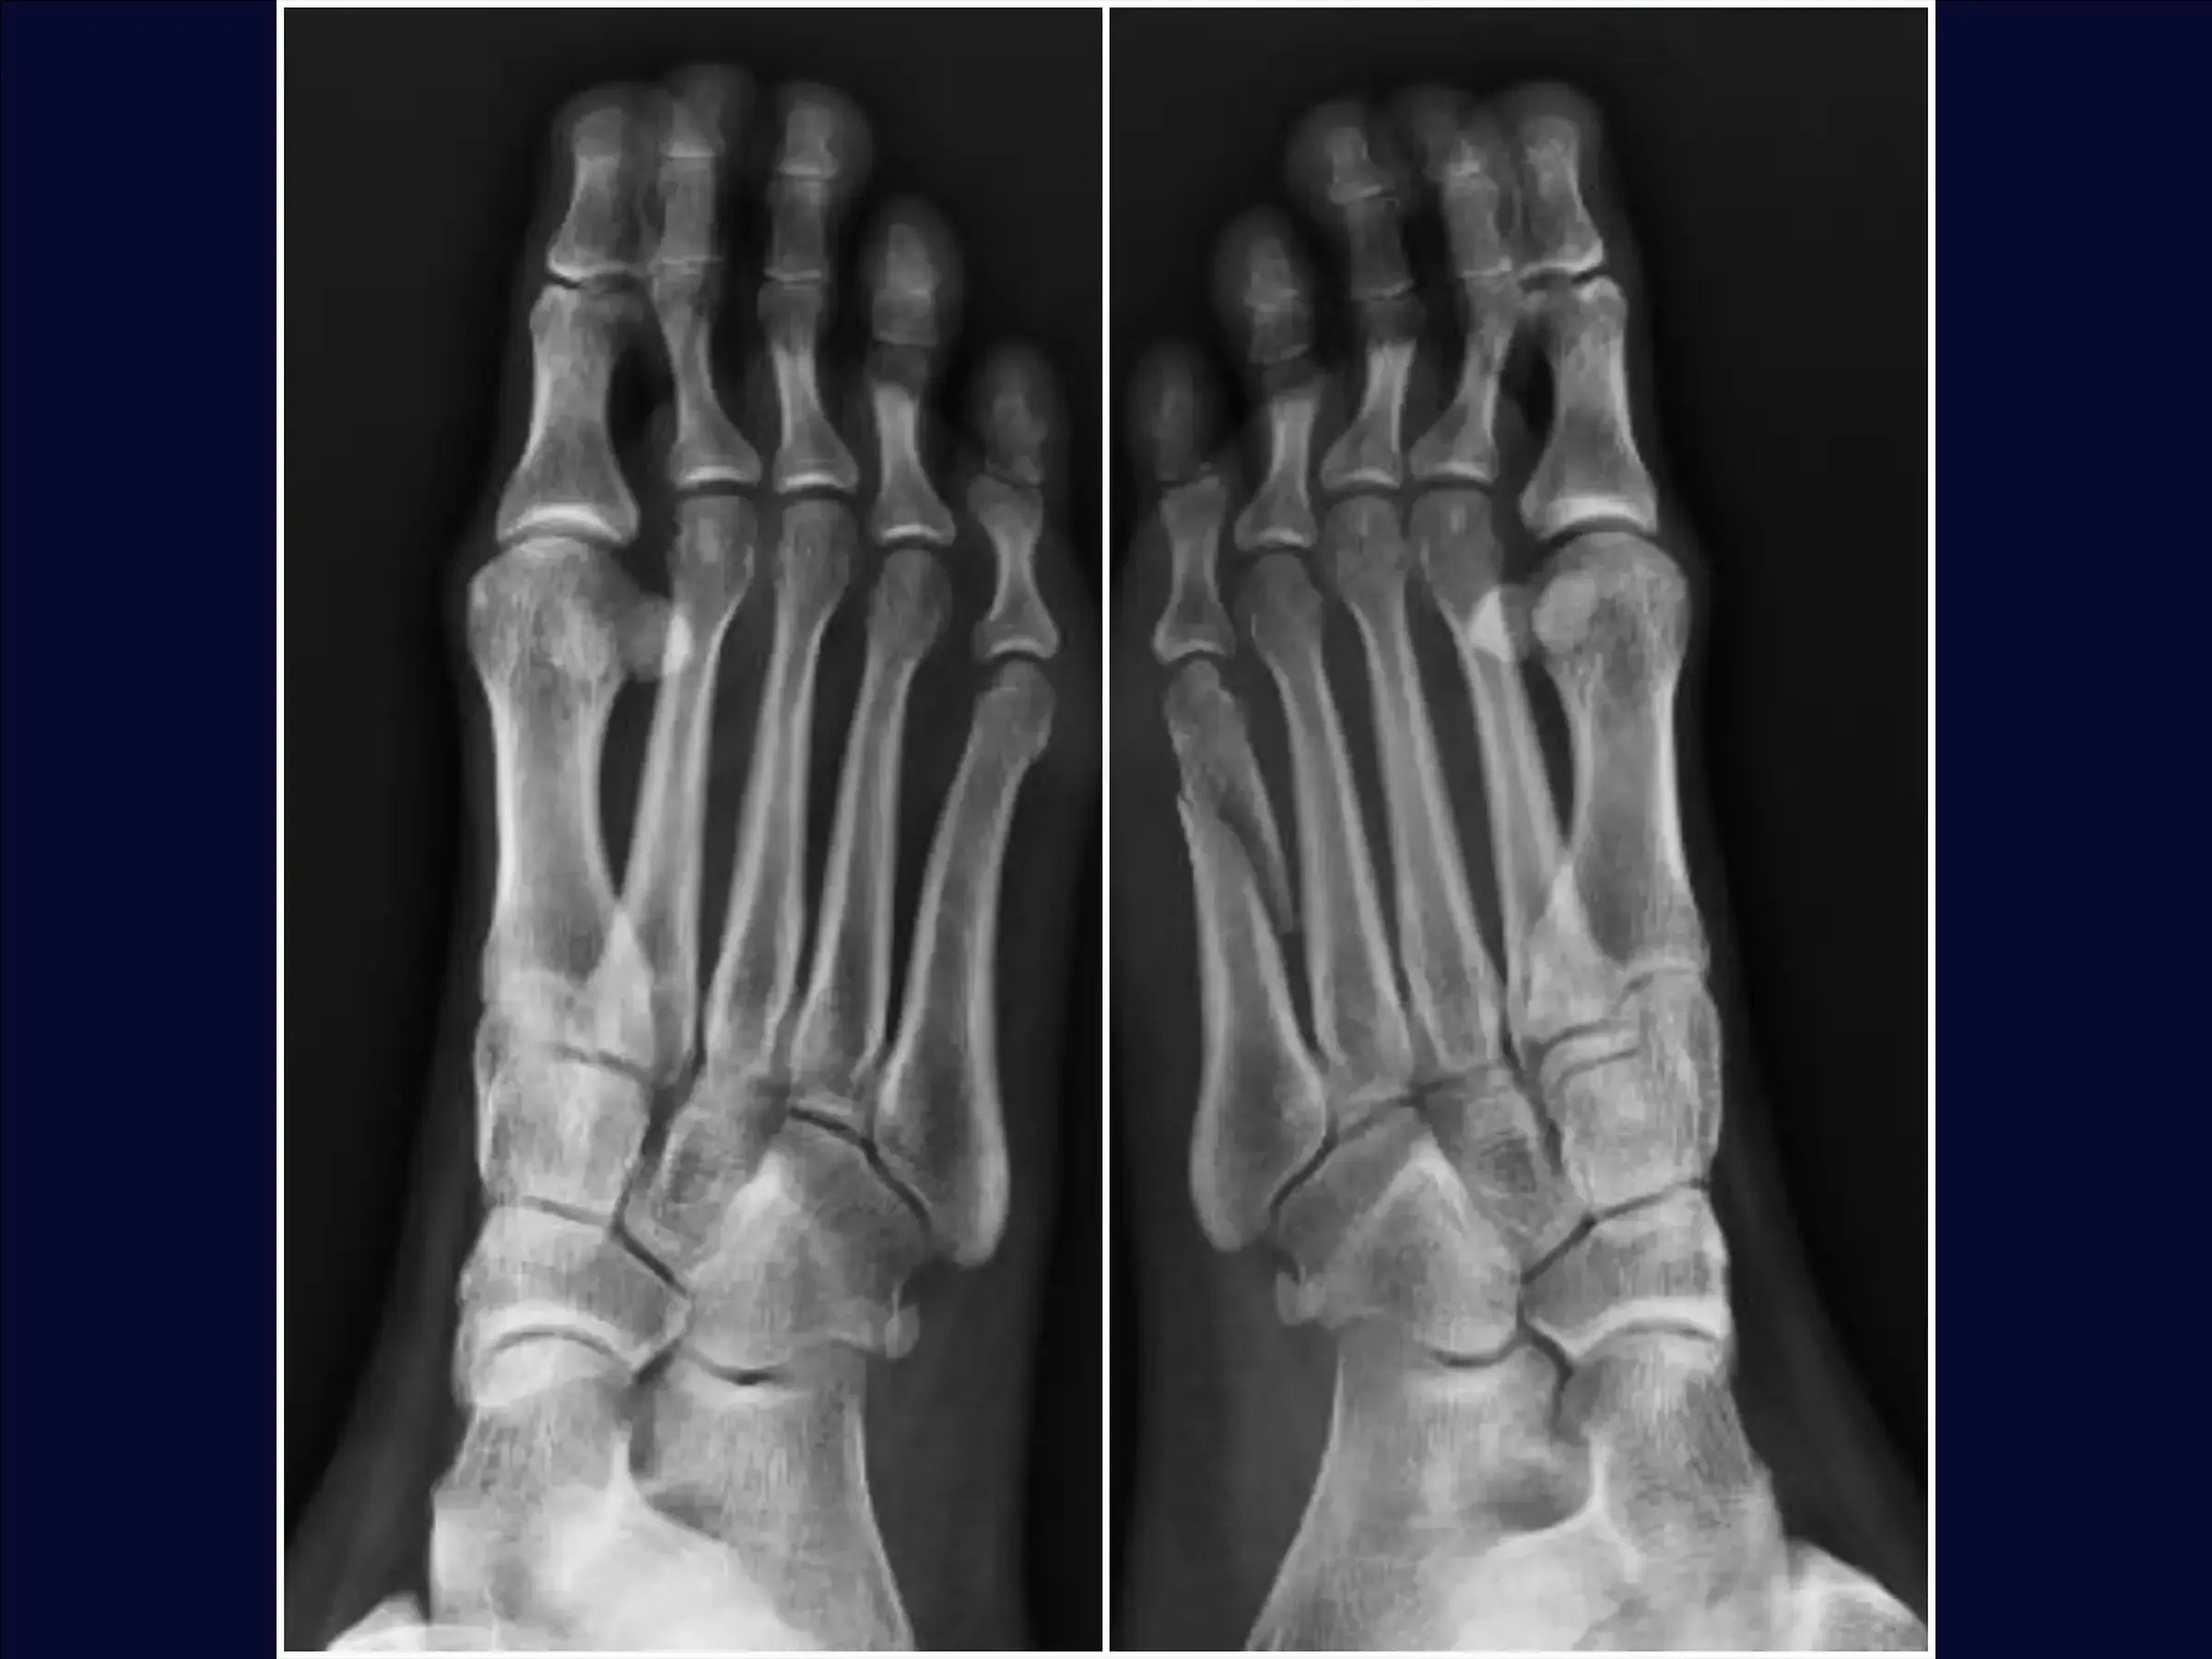

Mejore sus habilidades en el tratamiento quirúrgico de fracturas desplazadas del quinto metatarsiano. Este procedimiento requiere una reducción anatómica cuidadosa para evitar la metatarsalgia o la disfunción de la marcha, especialmente en pacientes jóvenes y atletas. Esta capacitación detalla el procedimiento quirúrgico con placa de bloqueo y tornillos, con énfasis en la rápida recuperación funcional y el retorno a la actividad deportiva.

- Evaluación y planificación del acceso: análisis de radiografías para identificar la angulación de la fractura y la posibilidad de alteración de la carga de peso, metatarsalgia o disfunción de la marcha.